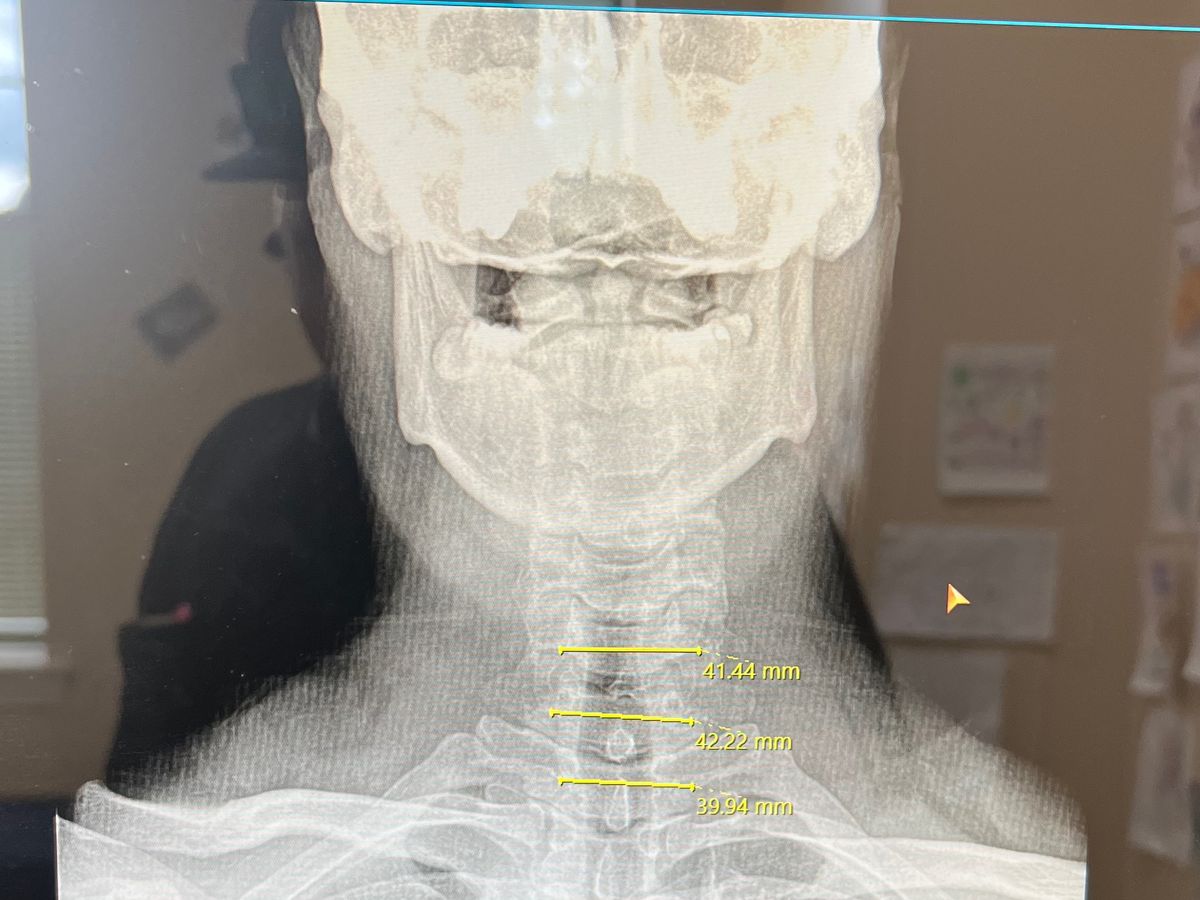

Hello, my name is Jeremy. Recently I found out I have a herniated disc between C4 and C5. This has left me with serious pain in my neck and very limited range of motion with no strength in my left arm. As I have managed to continue to work for the past several months with this, I found out today I will be going in for surgery on the 19th. This will leave me out of work for at least a month, if not longer. I am asking for help to continue to support my family, and pay bills while I am unable to work. Thank you for anything and everything from everyone, we appreciate all of you.